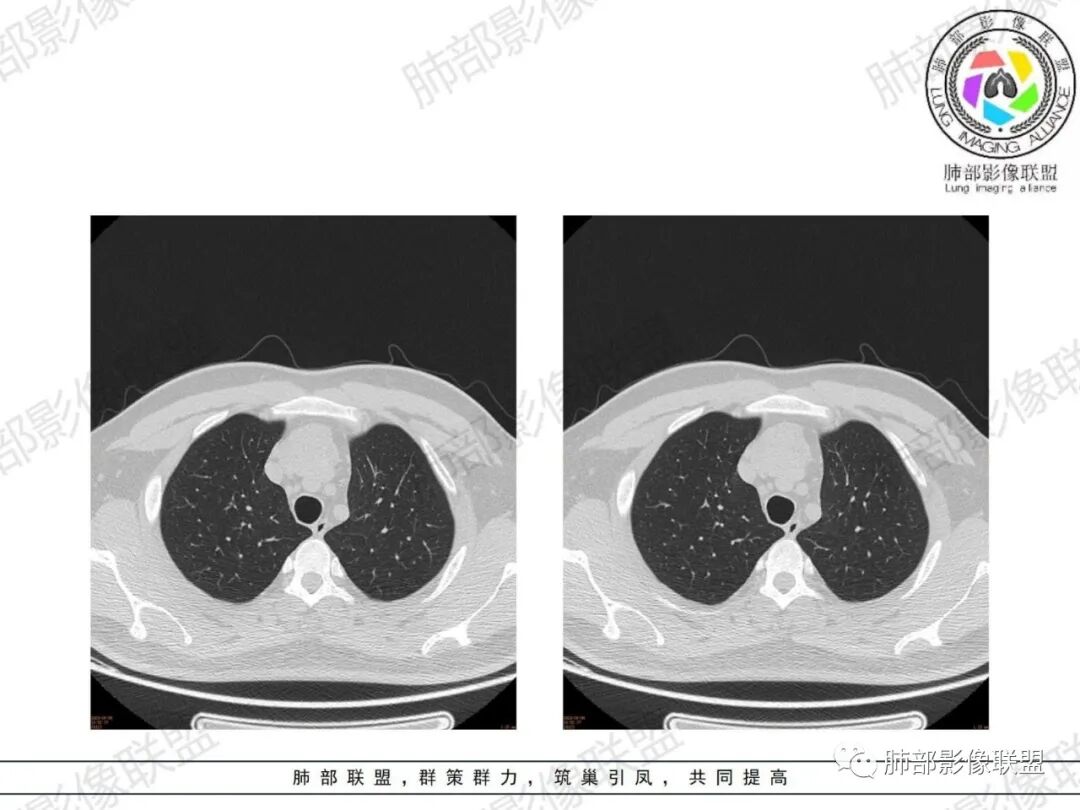

胸腺增生CT表现

体积、形态:

弥漫性增大,两缘对称,质地柔软,部分淋巴性胸腺增生的大小正常;形态保持其正常形态,呈类圆形、梨形,边缘光滑,可呈浅分叶

密度:

密度均匀,呈肌性密度,偶见细小钙化,其内有脂肪浸润样密度影

强化:

轻度或无强化

与周围结构关系:

与周围大血管、胸骨等周围组织结构分界清楚,无淋巴结肿大、胸膜及心包受累。

1、年轻男性,双下肌乏力,胸部CT提示前纵隔胸腺区病变,应当怀疑胸腺增生或胸腺瘤导致的重症肌无力。

2、前纵隔梨形软组织密度影,与正常胸腺形态一致,为胸腺弥漫性增大,两缘匀称,质地柔软,未见明显膨隆,其内可见脂肪浸润影,与周围结构分界清楚,再加上病人年龄,需要高度提示胸腺增生(淋巴滤泡样增生型)。胸腺瘤一般无脂肪浸润,质地较硬,呈结节或肿块状,且发病年龄较大。B2B3型肿块边界不清,可侵犯临近组织脏器,B3可胸膜转移,胸腺癌可引起纵隔淋巴结及远处转移。